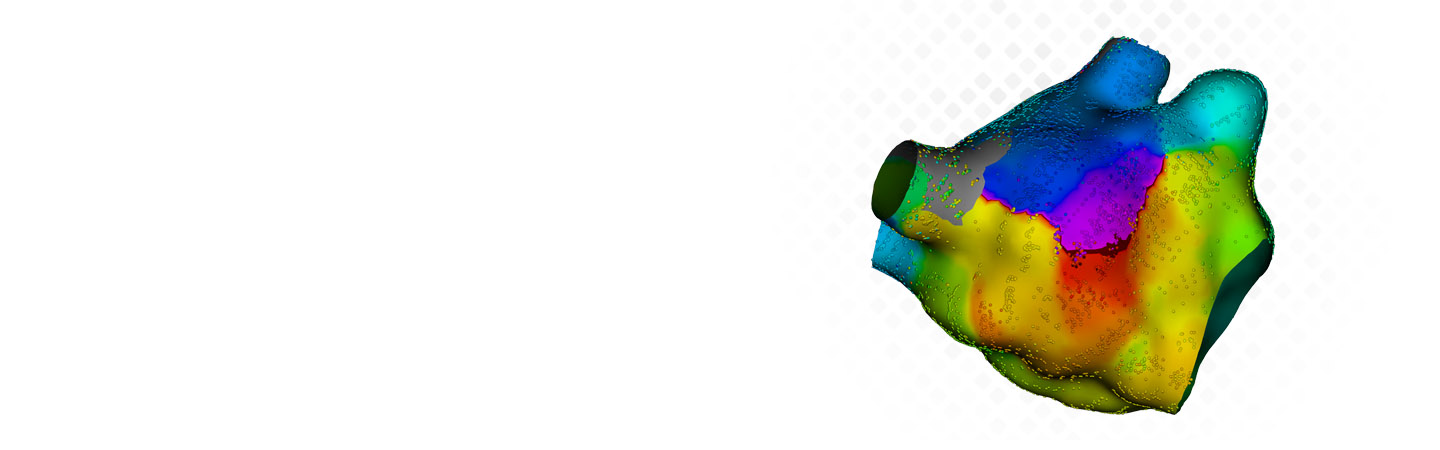

RHYTHMIA HDx Software

Featuring a continuous cardiac mapping algorithm that rapidly processes a high volume of data, RHYTHMIA HDx software creates high-definition maps that, studies have shown, offer more accurate and precise display of areas of interest, even in heavily diseased or scarred tissue.1

LUMIPOINT™ Software Module

RHYTHMIA HDx sets the standard with its high-density, high-resolution 3D maps, providing a level of clarity that enables accurate visualization of even the most complex activation patterns. Now, with the LUMIPONT Softward Module, you can harness this HD data to accelerate clinical decisions and enable effective minimum ablation.